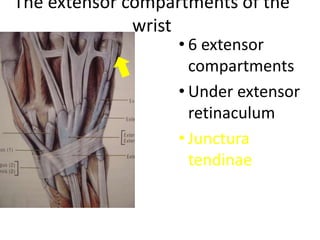

- It describes flexor tendon zones, extensor compartments, and pulley system anatomy.